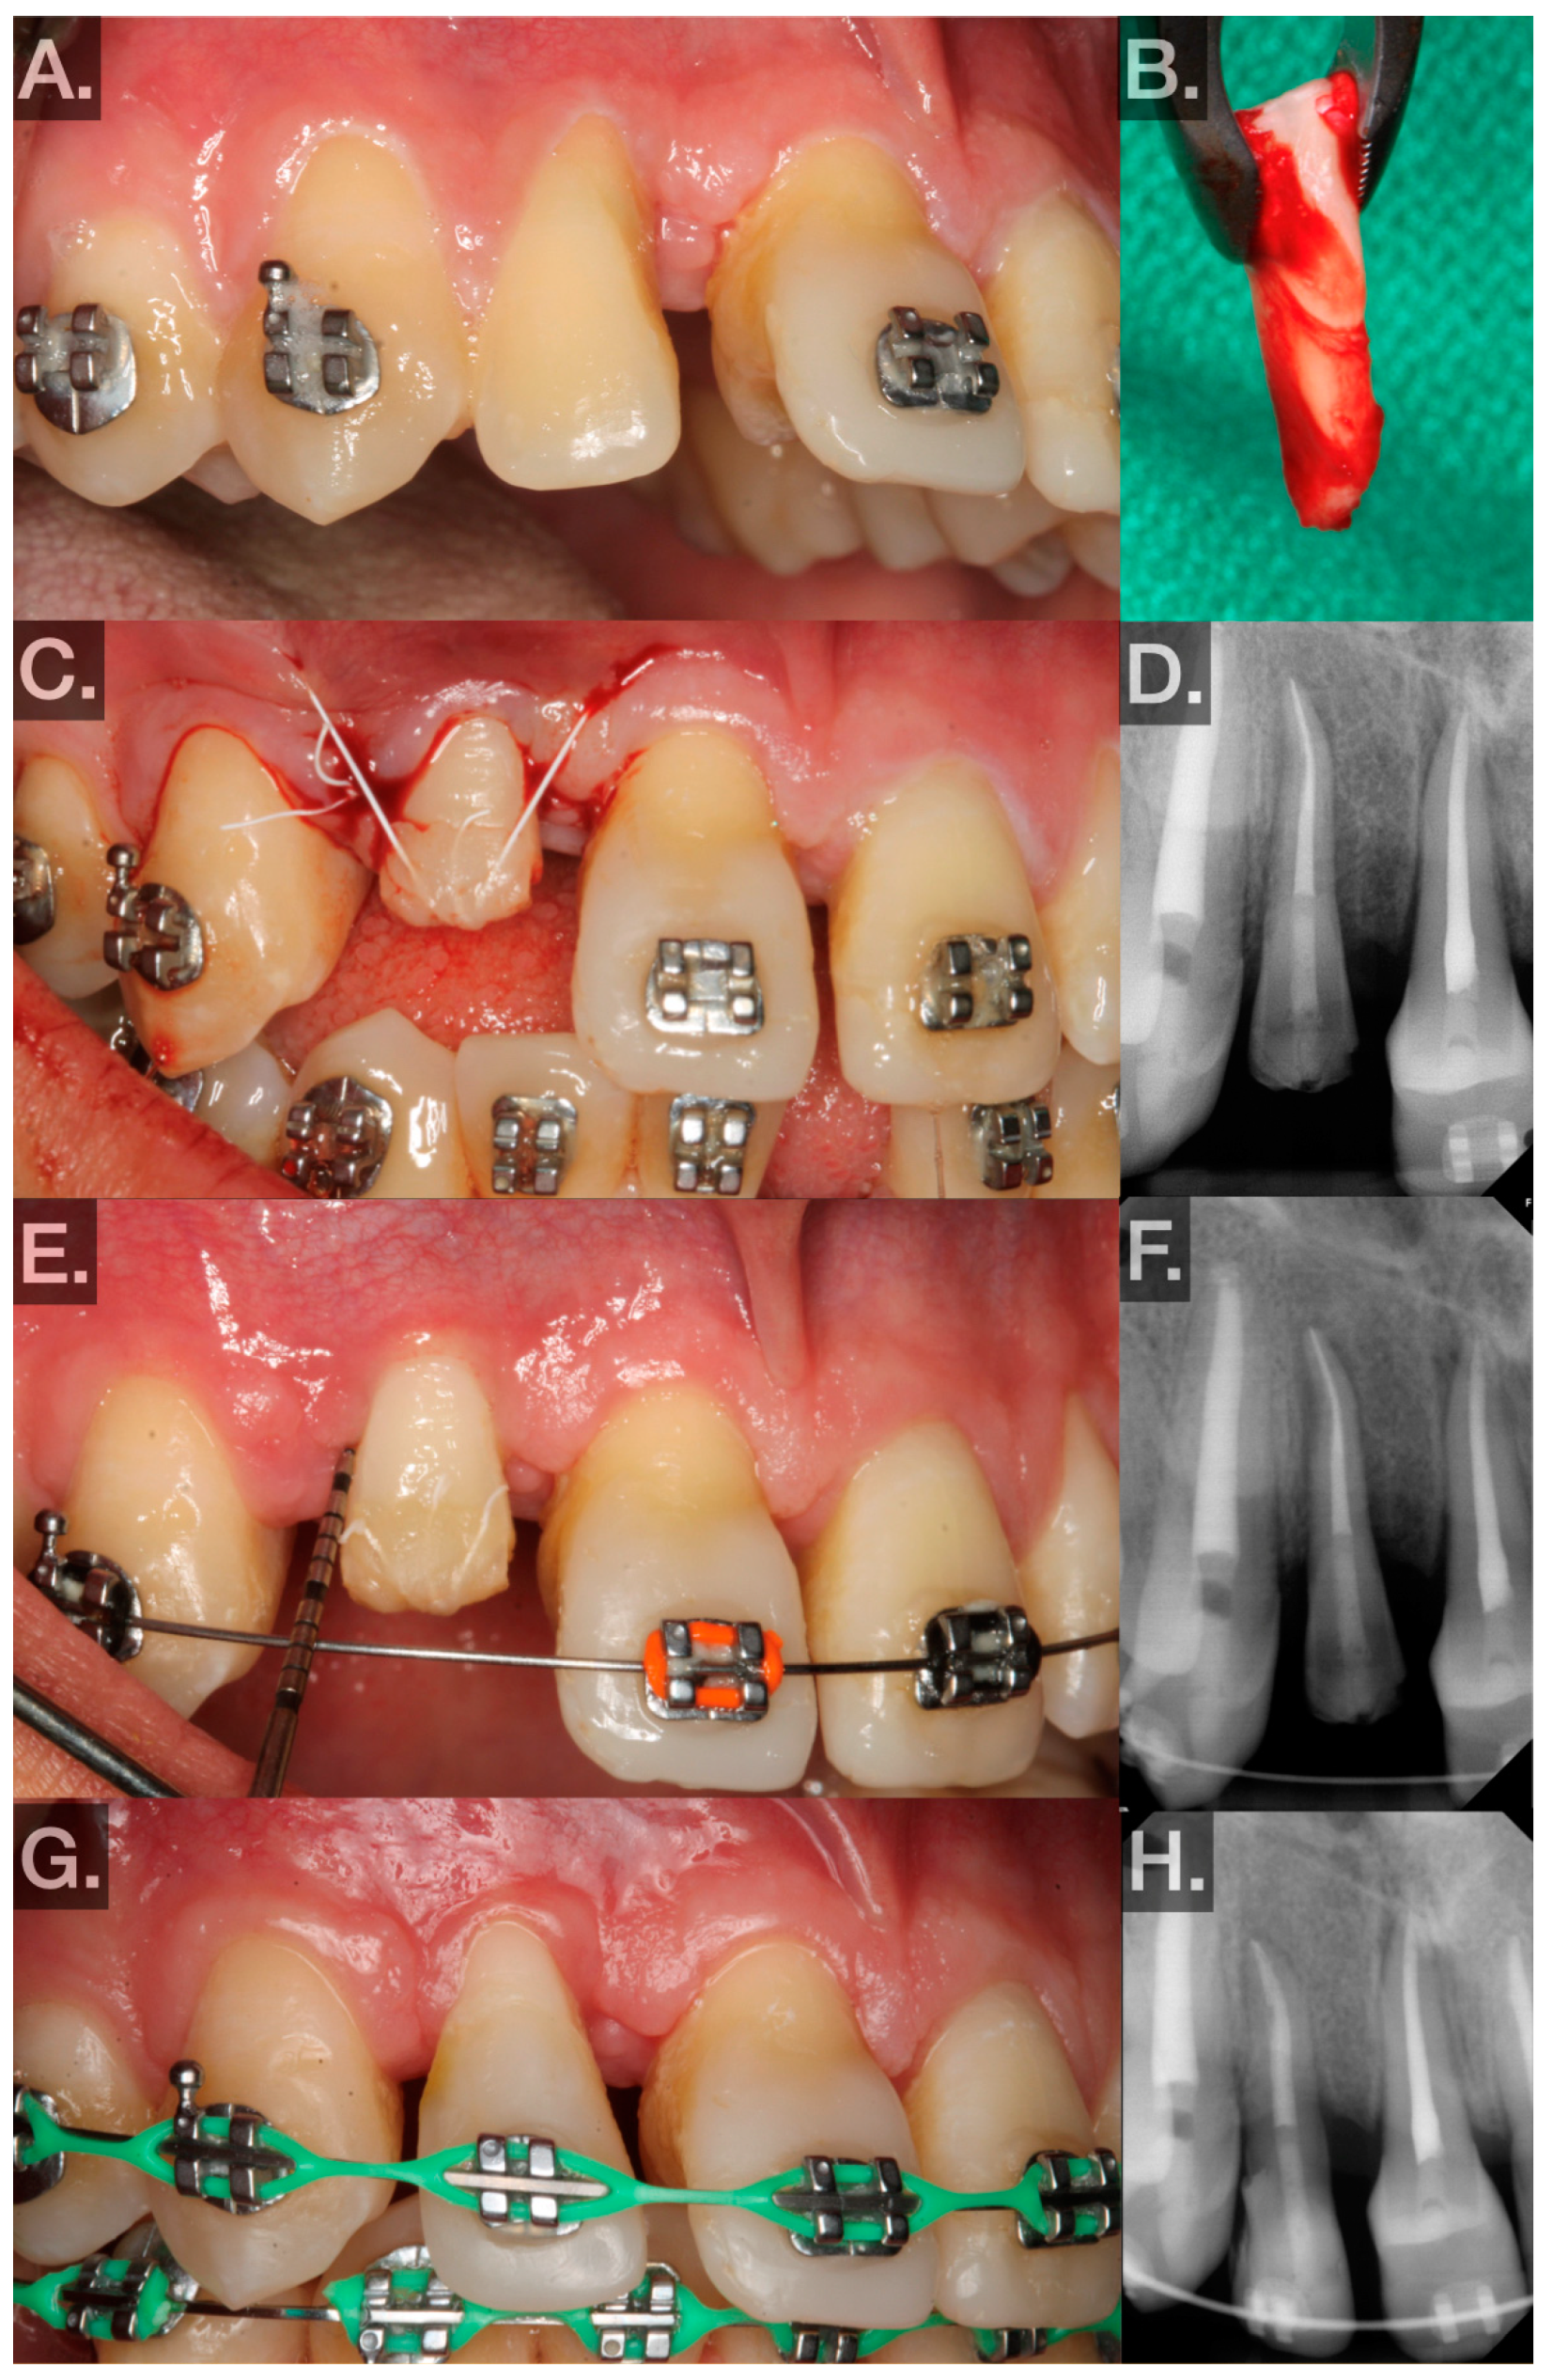

- No. 29 (FDIn no. 45) → no. 8 (FDIn no. 11) (Figure 2A–H; 5/2023):- ▪

- Two carpules of Septocaine® (articaine hydrochloride 4% and epinephrine 1:100,000; Septodont, Saint-Maur-des-Fossés, France) were used to anesthetize the donor tooth and recipient site through local infiltration. A midcrestal incision was made and a full-thickness flap was elevated in the tooth no. 8 (FDIn no. 11) area. The recipient site was then prepared by creating an osteotomy using an implant motor (Implant 900, Denstply Sirona, Charlotte, NC, USA) and implant drills (Bone Level Tapered Drills, Straumann AG, Basel, Switzerland.) The osteotomy was prepared to be slightly larger than the measurements made on the CBCT. Part of the buccal plate was intentionally obliterated in order to place the tooth in a proper buccolingual location. After the recipient site was prepared, the replica of the donor tooth was tried in (Figure 2B). Passive fit and subocclusal positioning were verified. Luxation forces were made with forceps on tooth no. 29 (FDIn no. 45) using slow rotational movements only. Special care was taken to ensure the beaks of the forceps did not seat apical to the CEJ. Tooth no. 29 (FDIn no. 45) was then extracted atraumatically and immediately placed into the artificially created socket at the site of tooth no. 8 (FDIn no. 11). The extra-alveolar time was less than 30 s. The tooth was fixated in the recipient site with 4–0 polytetrafluoroethylene (Cytosurg® PTFE, Salvin, Charlotte, NC, USA) sutures via a Laurell–Gottlow suture technique [22]. Simple interrupted sutures were also used to approximate the tissue interproximally (Figure 2C). A periapical radiograph was then taken to serve as a baseline to evaluate healing (Figure 2D).

- Postoperative visits at 1, 3, and 6 weeks and 3, 6, and 12 months were planned.- ▪

- At 1 week, sutures were removed, and the patient was instructed to use a soft surgical toothbrush (Rx Ultra Suave, PHB Toothbrushes, Osseo, WI, USA) dipped in chlorohexidine twice daily to clean the clinical crown of the transplant for 2 weeks.

- ▪

- At week 3, bleeding on probing (BOP), probing depth (PD), and mobility were measured at 6 sites to evaluate periodontal healing (Figure 3E). The patient was instructed to resume normal brushing and to use the tooth in normal function.

- At week 6, BOP, PD, and mobility were measured at 6 sites to evaluate periodontal healing.

- Between weeks 6 and 8, the transplanted teeth were restored with composite resin (Filtek™ Supreme Ultra Universal Restorative, 3M™, Saint Paul, MN, USA) and orthodontically loaded with low-force 0.016 NiTi wires. Special care was taken at this point to avoid intrusive orthodontic forces.